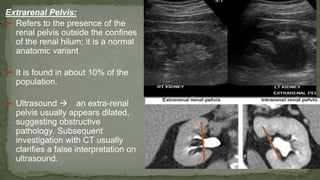

Extrarenal Pelvis:

➢ Refers to the presence of the

renal pelvis outside the confines

of the renal hilum; it is a normal

anatomic variant

➢ It is found in about 10% of the

population.

➢ Ultrasound  an extra-renal

pelvis usually appears dilated,

suggesting obstructive

pathology. Subsequent

investigation with CT usually

clarifies a false interpretation on

ultrasound.